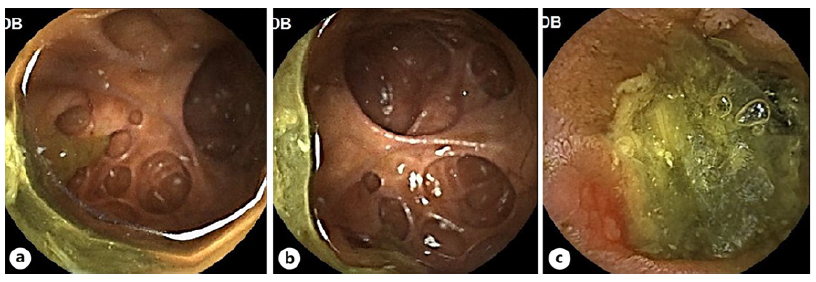

After receiving intravenous iron supplementation, she was discharged to a gastroenterology consultation, where a small bowel capsule endoscopy was requested to proceed with the iron deficiency anemia etiologic investigation. By this time, the patient denied having abdominal pain and vomiting in the previous months. This examination was incomplete due to capsule retention in a segment with multiple diverticula with friable mucosa (shown in Fig. 1a-c). Capsule expulsion was later con-firmed by the patient.

Fig. 1 a-c Jejunal diverticulosis identified in small bowel capsule endoscopy, with friable mucosa in (c).